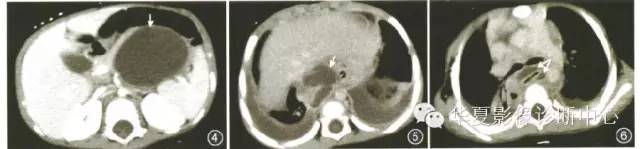

胸、腹部联合CT增强检查示:胰腺体尾部见囊状低密度灶,边界尚清,最大断面60mm×50mm,病变经食管裂孔与纵隔内囊状低密度灶相连,且向上延伸至颈根部。双侧胸膜腔背侧见新月形低密度影,提示胰体尾部假性囊肿伴胰胸瘘(图4~6)。

图4~6例2。CT示胰腺体尾部囊状低密度灶(图4,箭),大小60mm×50mm。胰腺假性囊肿通过食管裂孔与纵隔假性囊肿相交通(图5,箭),假性囊肿延伸至颈根部(图6,箭),双侧胸腔积液